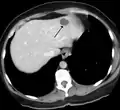

Hemangioma of the liver as seen on ultrasound

A liver hemangioma as seen on CT